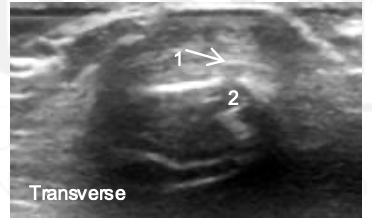

What view is this?

PIP

Synovium

Extensor Tendon

Proximal Phalanx

Middle Phalanx